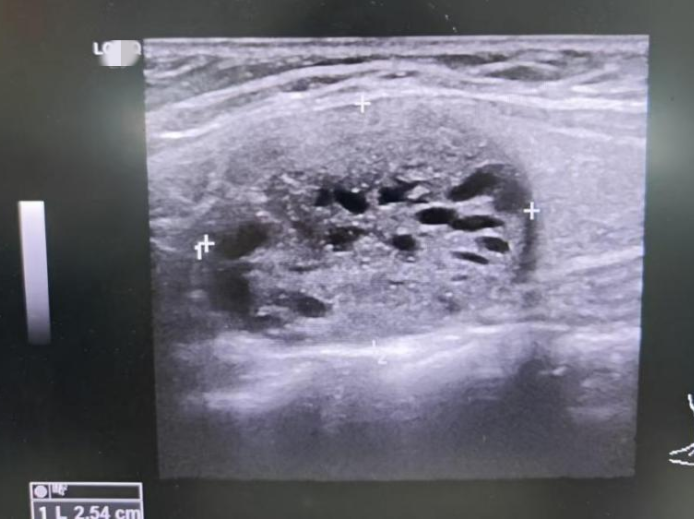

随后的一系列检查,终于揭开了“轻轻一推就骨折”的真相:瑞瑞的血甲状旁腺激素水平飙到501.2ng/L,是正常值(18.5-88.0ng/L)的近6倍;甲状腺超声更显示,他左侧甲状腺下极背侧有个实性占位(大概率是甲状旁腺来源的肿瘤)。

这应该是导致骨折的“元凶”。甲状旁腺肿瘤会引发原发性甲状旁腺功能亢进症,过量的甲状旁腺激素会打乱身体钙磷代谢,导致血钙升高、骨质密度降低,让骨骼变得“脆弱不堪”,所以妹妹那轻轻一推,才会让原本该结实的股骨轻易骨折。